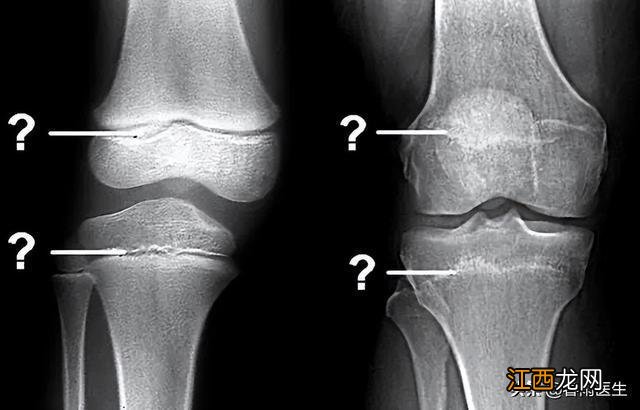

所以成年并不是长高的决定性因素 , 骨骺才是 。那么,如何知道自己的骨骺有没有闭合呢?很简单,去医院拍个片就一目了然了 。

(左为未闭合,右为已闭合/图源网络,侵删)